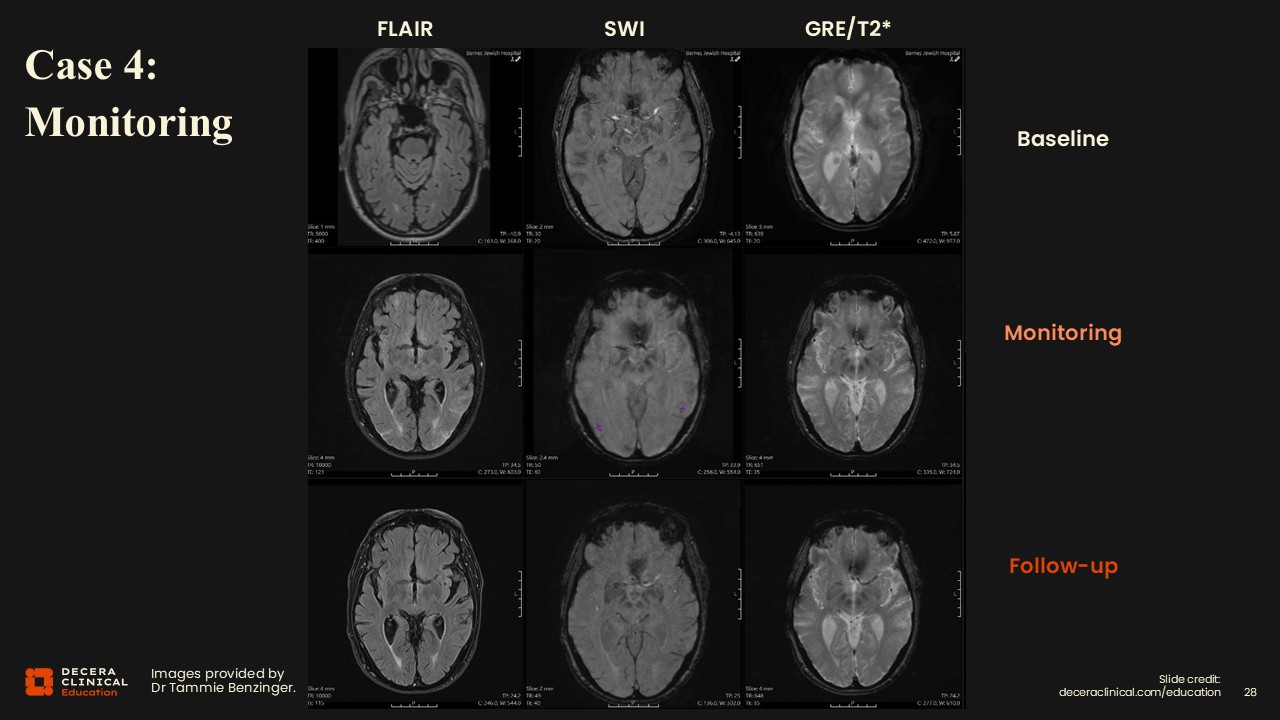

Case 4: Moderate ARIA-E and ARIA-H

Dr Benzinger:

This is a nice example of edema and effusions on FLAIR having similar findings on SWI for siderosis.

Case 4: Moderate ARIA-E and ARIA-H (Detail)

Purple arrows in the inset images show areas of interest; again, the 2 findings occur in the same brain regions.

Case 4: Moderate ARIA-E and ARIA-H (Grading)

Classification for ARIA-E will be moderate because there were 2 different regions less than 10 cm each. For ARIA-H, there were 2 regions of siderosis, so that classification is moderate as well. Our actions would include notifying the clinical team, documenting the grading in our report, and recommending a follow-up MRI for stabilization vs progression. The clinical team will correlate symptoms and determine whether therapy should be paused under the treatment algorithm. Once a case falls into the moderate range, therapy would typically be paused until ARIA resolves/stabilizes.